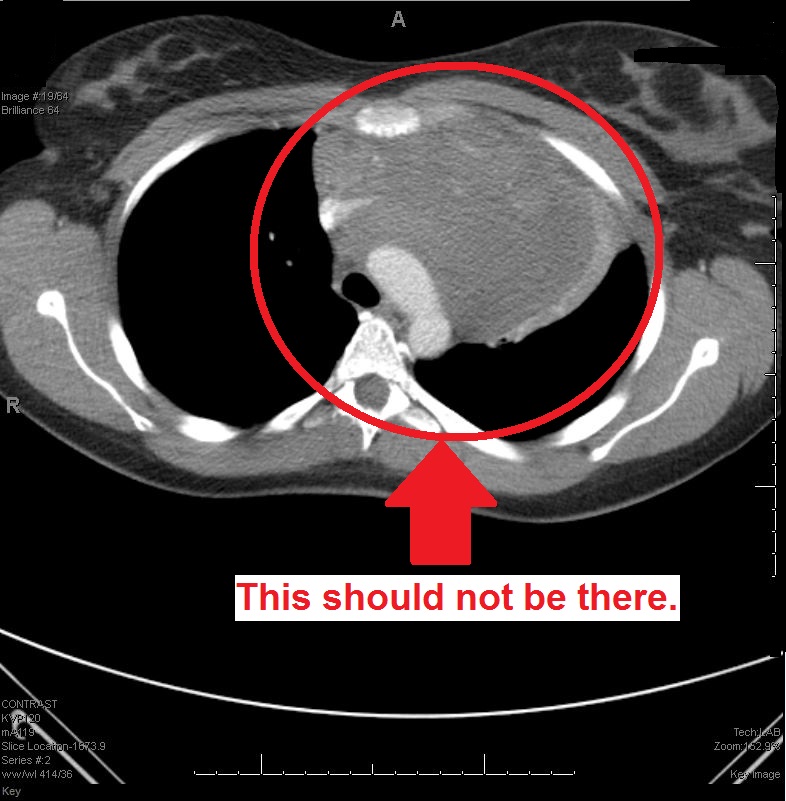

He took Dad and I into another room, a little closet of a room with a few computer monitors and my imaging lab work pulled up on them.

He showed us what my insides looked like at the moment.

I didn’t care. I would just do whatever the doctor said was best, because Dr. SeriousFace clearly knew his business. His face was so serious. It conveyed a lot of confidence. It could be a few different things. Dr. SeriousFace told us. It could be a thymoma, or some form of lymphoma. We wouldn’t know until the biopsy was complete and the results could be analyzed.

We picked a needle biopsy.*** It was the least invasive. It would leave me less scarred, and it wasn’t exactly like they could miss the giant thing growing in my chest.